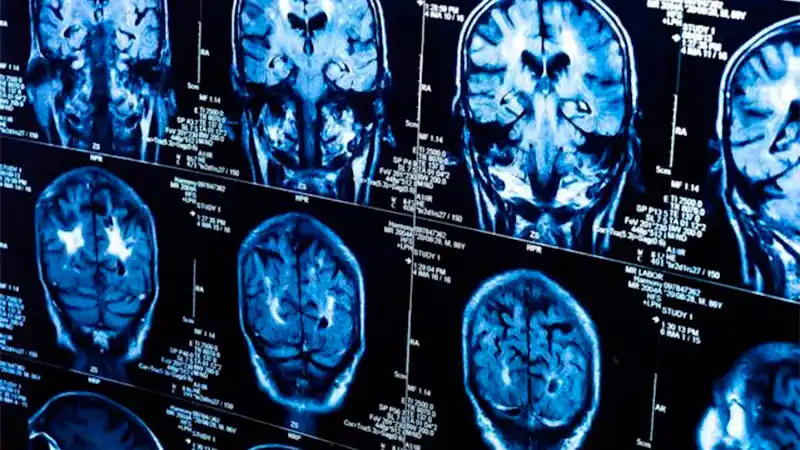

Un doble escáner, uno realizado antes de la pandemia y el otro en los peores meses de la crisis, muestra que los infectados por el coronavirus tienen cambios en el cerebro no vistos en los que han escapado al virus. El estudio muestra que el descenso de materia gris es generalizado, y que las áreas más afectadas son las relacionadas con el olfato. Los autores del trabajo no saben si estos daños son provocados por el virus en sí o son consecuencia de la enfermedad. Tampoco saben si temporales o serán para siempre.

Ahora, un grupo de investigadores de la universidad de Oxford (Reino Unido) ha podido analizar las imágenes del cerebro de casi 800 británicos. El estudio es longitudinal, es decir con datos del mismo grupo de personas en distintos momentos. Eso otorga un extra de robustez a sus resultados. La mitad de los participantes tuvieron Covid entre una resonancia y otra, tomadas con más de tres años de diferencia, lo que ha permitido comparar los cambios inducidos por el coronavirus en el cerebro y cotejarlos con las imágenes cerebrales de los no afectados.

Los resultados, publicados en la revista Nature, muestran que los infectados tenían una mayor pérdida de materia gris y más alteraciones en los tejidos cerebrales. Las diferencias eran más grandes en las partes del cerebro que intervienen en el sentido del olfato, como la corteza orbitofrontal o el giro parahipocampal. Todos estos cambios eran más acusados cuanta más edad tenían los participantes.

La investigadora del Departamento Nuffield de Neurociencia Clínica de Oxford y principal autora del estudio, la profesora Gwenaëlle Douaud, destaca que también han visto “diferencias en regiones no relacionadas con el sentido del olfato, como el polo temporal, el giro supramarginal o el cerebelo”. En cuanto al volumen global cerebral, “hubo una pérdida adicional de un 0,3% entre los participantes infectados”, añade. Esa es la media, pero hay casos de una reducción del total del cerebro del 2%, porcentaje aún mayor en las regiones olfatorias. De nuevo, el deterioro era comparativamente, superior cuanta más edad tenía el sujeto.